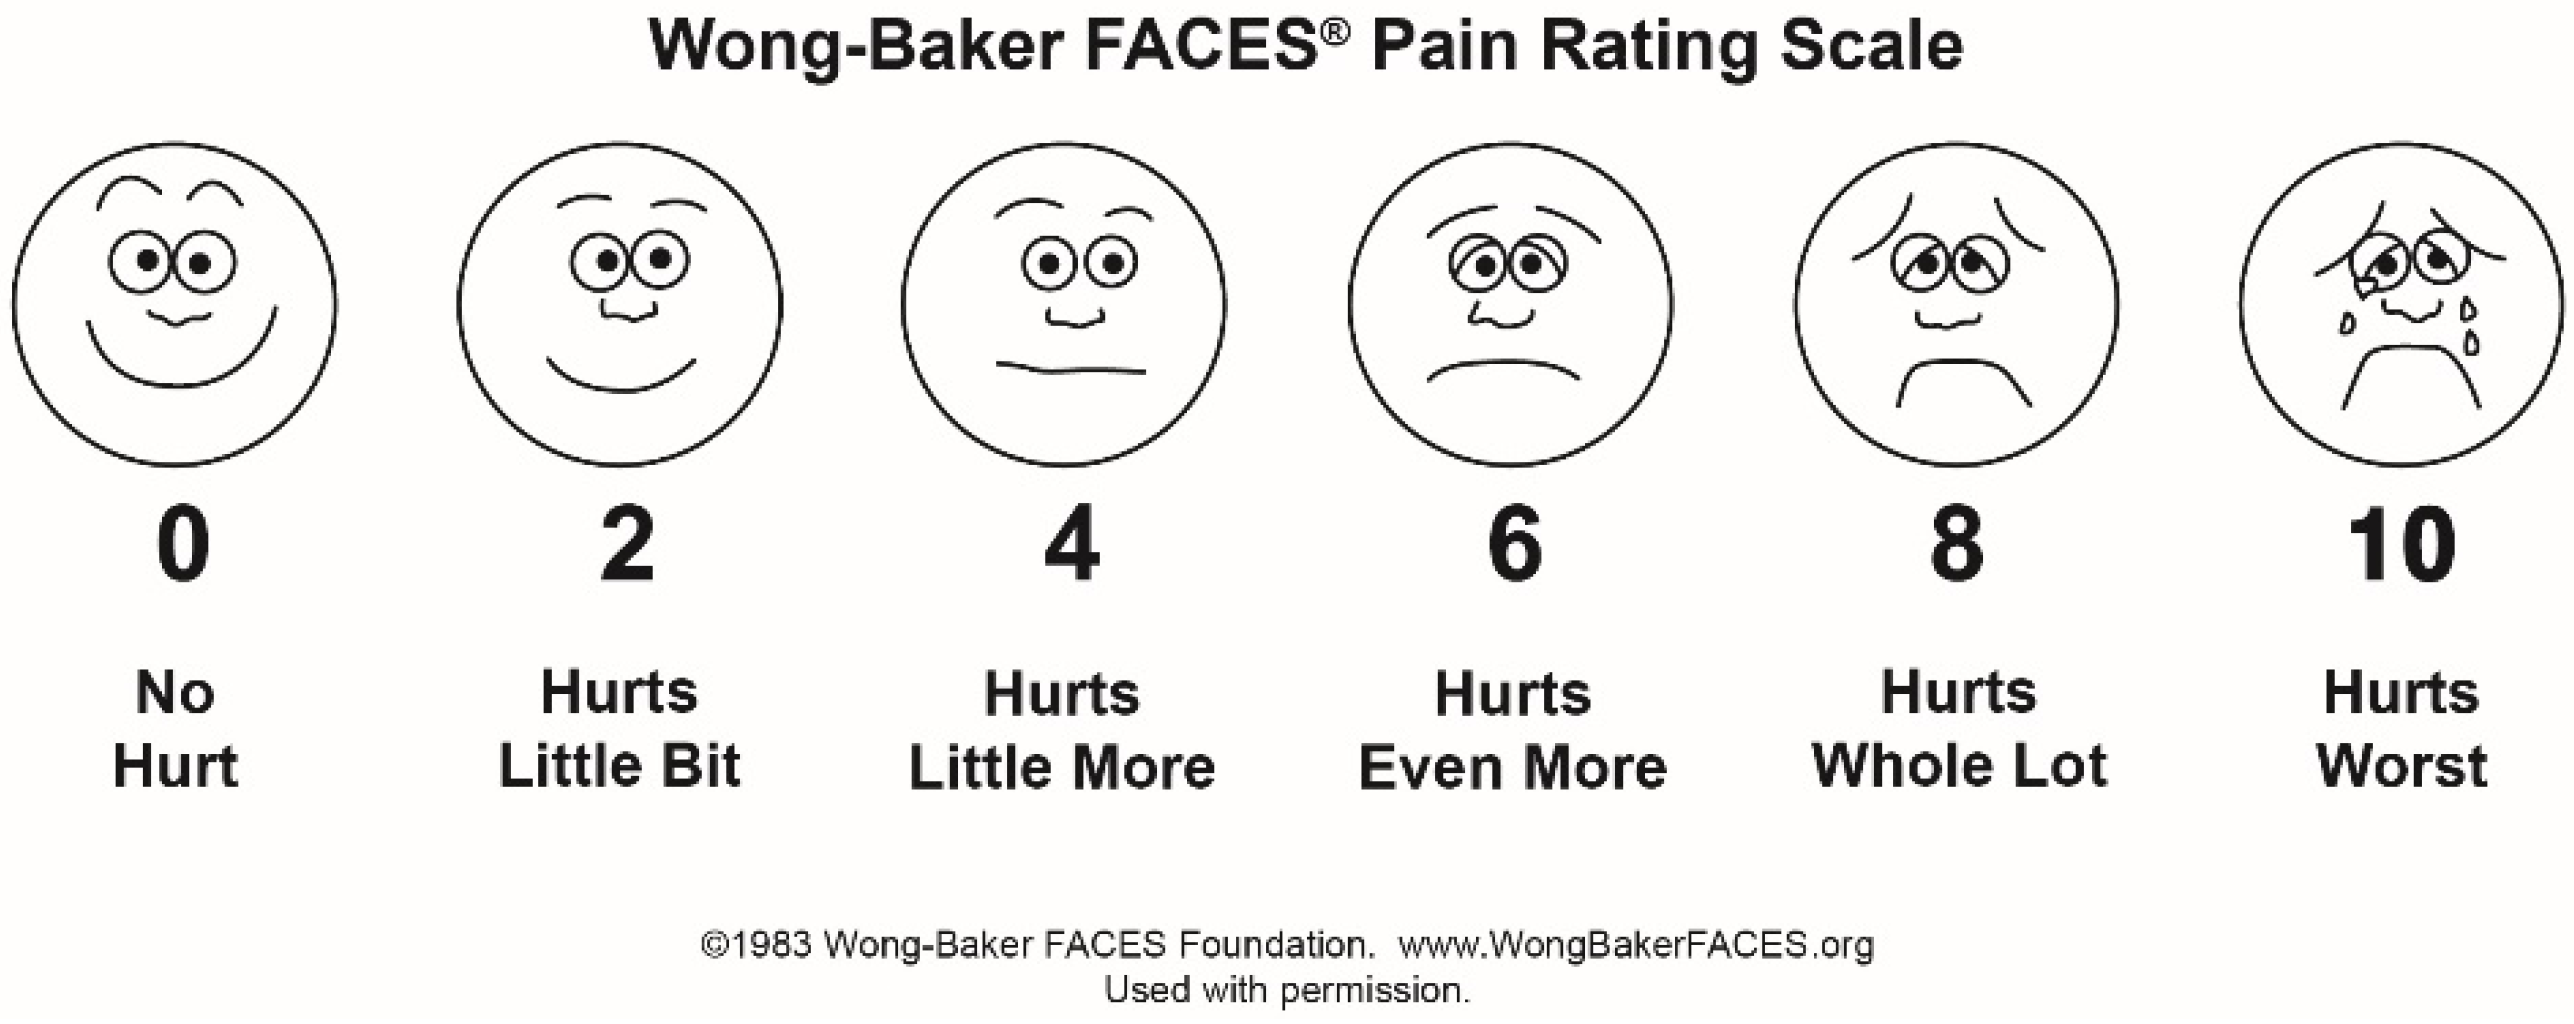

2.5. The Working Technique

2.6.3. Analysis of the Laser Doppler Flowmetry Measurements

3. Results